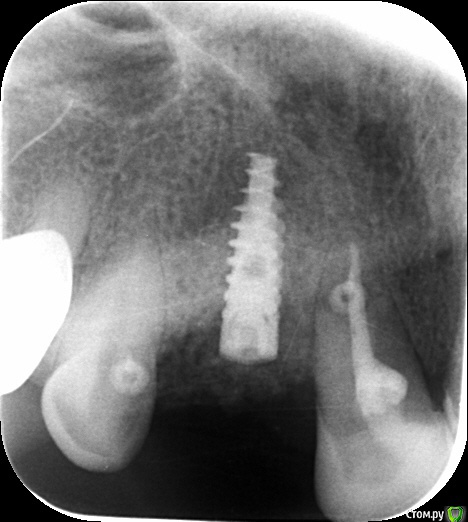

an_ver Опубликовано 12 июня, 2015 Поделиться Опубликовано 12 июня, 2015 История такая.2 месяца назад,поставил SPI 3,75*13 в область ранее удаленного 13 (удалял не я; после удаления прошло 12 недель),щелевидный деффект, торк 25,мр3,эволюшн,небно на шов,вестибулярно на пины. Вчера позвонила,пришла, свищ! Гутту,в заглушку опирается.Закрутить формик? Не рано? По снимкам разница 2 месяца. Ссылка на комментарий

Aquarius Опубликовано 12 июня, 2015 Поделиться Опубликовано 12 июня, 2015 Снимки местами перепутаны? Может просто заглушечный свищ? Открыть, отмыть, ФДМ? 2 Ссылка на комментарий

an_ver Опубликовано 13 июня, 2015 Автор Поделиться Опубликовано 13 июня, 2015 Снимки местами перепутаны? Может просто заглушечный свищ? Открыть, отмыть, ФДМ?Перепутаны. Ссылка на комментарий

an_ver Опубликовано 15 июня, 2015 Автор Поделиться Опубликовано 15 июня, 2015 Проблема была не в заглушке. Обратите внимание на светлую полосу над заглушкой.Кусок косточки(((,раскрыл,промыл,формирователь. 1 Ссылка на комментарий